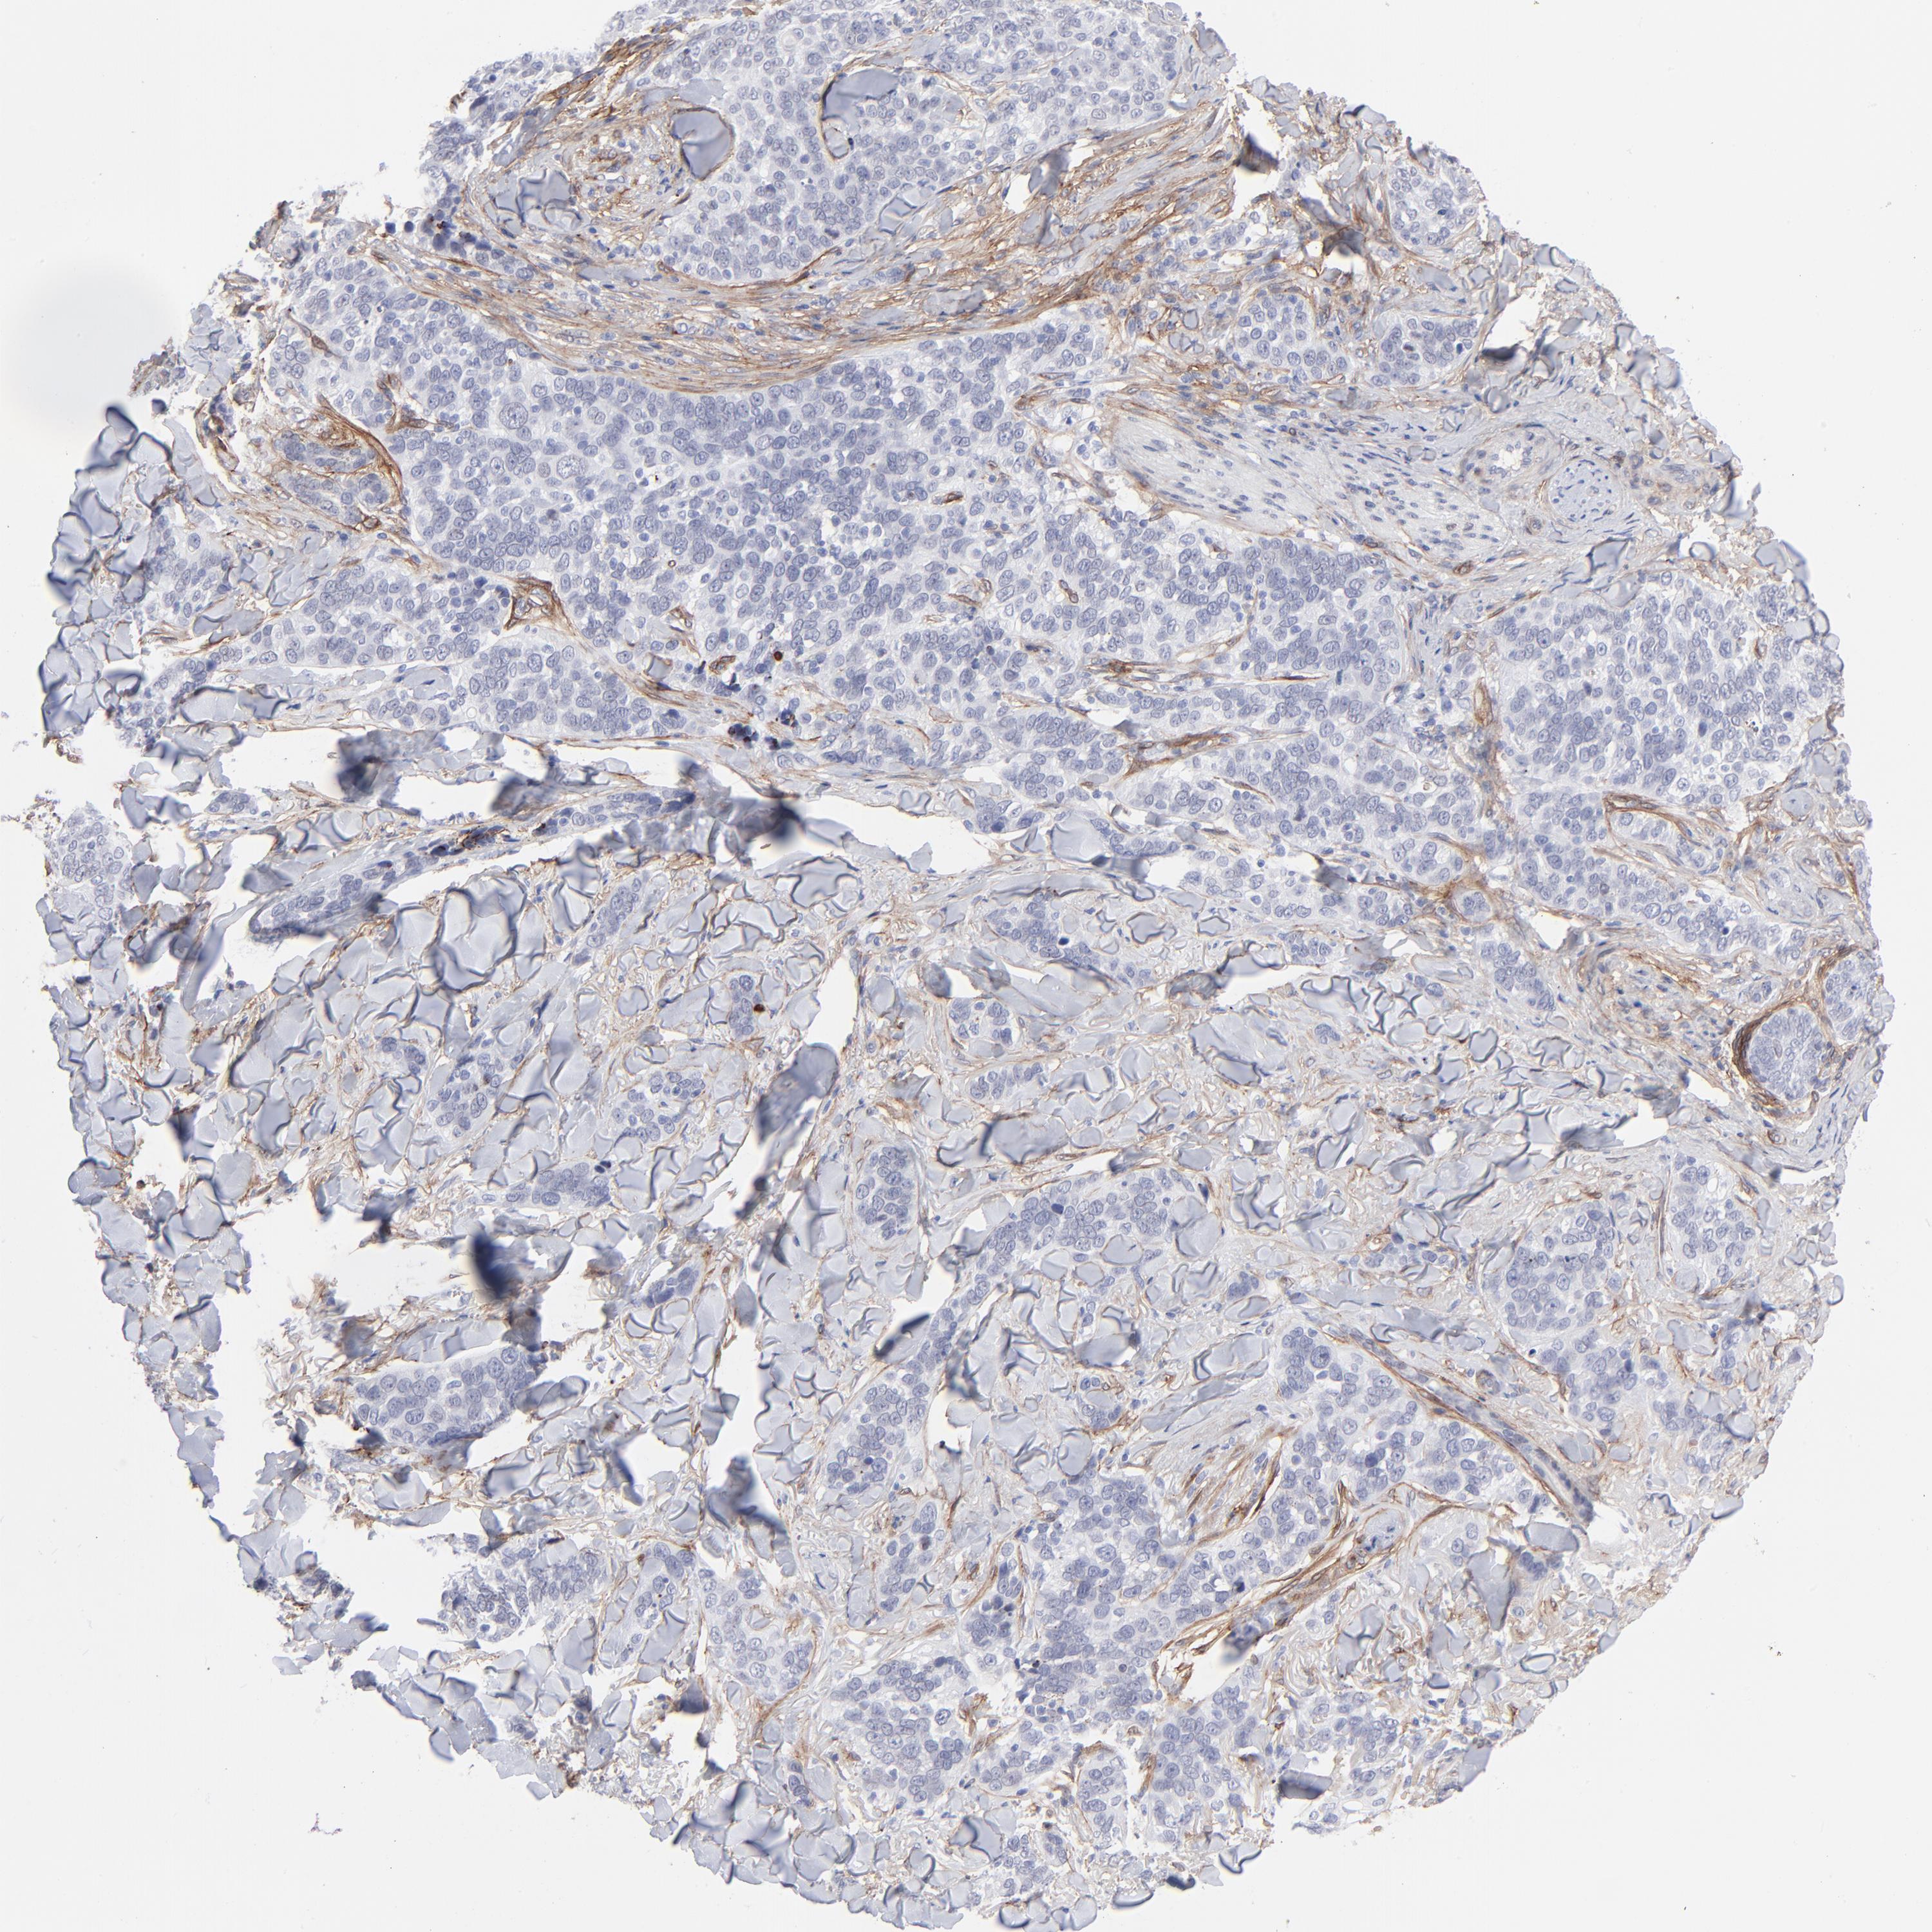

Basal cell and squamous cell cancer

SKIN CANCER - Protein expressioni

A mouse-over function shows sample information and annotation data. Click on an image to view it in a full screen mode. Samples can be filtered based on level of antibody staining by selecting one or several of the following categories: high, medium, low and not detected. The assay and annotation is described here.

Each image is clickable and will lead to virtual microscopy that enables deeper exploration of all samples and also displays staining intensity scores, fraction scores and subcellular localization as well as patient and tissue information for each sample.

Antibody CAB003842

Squamous cell carcinoma, NOS

Basal cell carcinoma

Squamous cell carcinoma in situ, NOS

Squamous cell carcinoma, metastatic, NOS